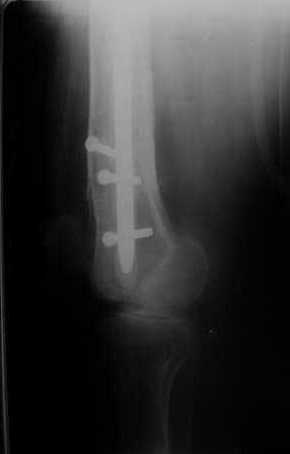

Мы демонтировали спице-стержневой аппарат, рассверлили костно-мозговой канал (до 14 мм), установили в канал спейсер с антибиотиком и произвели его блокирование четырьмя винтами ( рис. 1, 2, 3, 4).

В качестве армирующего элемента для спейсера мы использовали титановый неканюлированный штифт типа UFN (диаметр 9 мм, длина 400 мм). Проксимальную широкую часть штифта костным цементом не покрывали (рис. 5).

Дистальные блокирующие отверстия в цементе рассверлили после его застывания под ЭОП'ом. В проксимальном отломке использовали винт-полер (так как штифт проходил очень близко к переднему кортикальному слою).